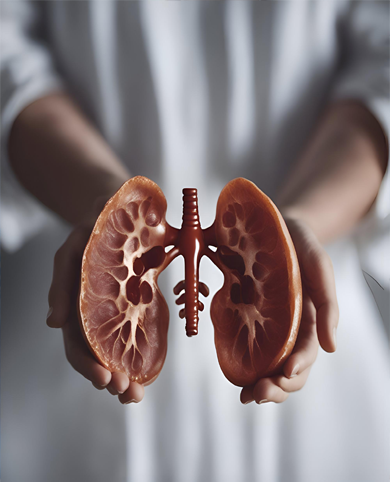

A specialized field in medicine and pharmaceuticals dedicated to the study, diagnosis, and treatment of kidney-related disorders. Nephroscience focuses on developing innovative medications and therapies to address conditions such as chronic kidney disease, renal failure, and other nephrological issues, aiming to improve overall kidney health and patient outcomes.